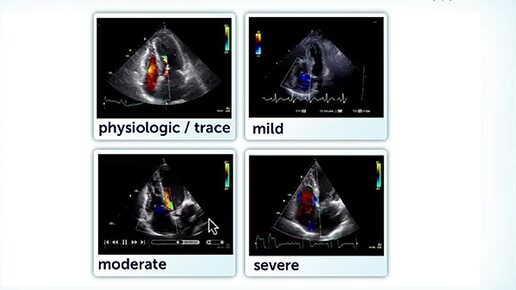

3. TR Quantification